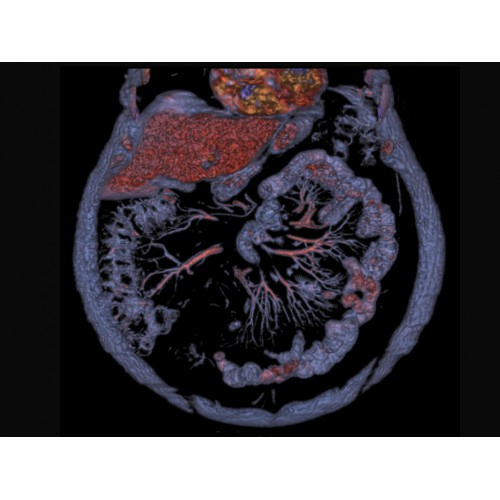

• Широкая область применения: от неврологии до кардиологии и онкологии.

КТ аппарат GE Optima CT520 используется для диагностики широкого спектра заболеваний:

Онкология

• Раннее выявление новообразований и контроль эффективности лечения.

• Планирование лучевой терапии с высокой точностью.

• 3D-реконструкция костных структур для планирования операций.